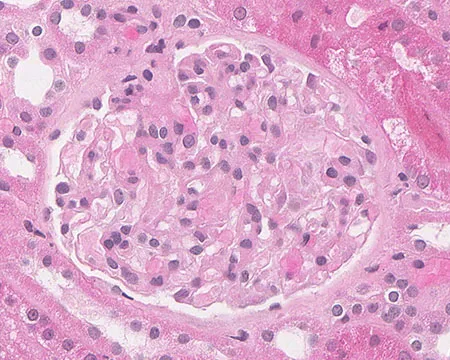

Amiloidose renal: aspectos sobre patogenia, diagnóstico e proteomica

Amiloidose renal: aspectos sobre patogenia, diagnóstico e proteomica

Este vídeo apresenta, de forma didática e baseada em evidências, os principais achados da tese de doutorado sobre amiloidose renal, com foco em proteômica glomerular e ativação do complemento. São discutidos aspectos diagnósticos, implicações fisiopatológicas e correlações clínico-patológicas relevantes para a prática do nefrologista. O conteúdo sintetiza dados inéditos de matriz extracelular glomerular e diferencia perfis entre subtipos de amiloidose. Trata-se de um material aprofundado e acessível, ideal para atualização de especialistas na área.